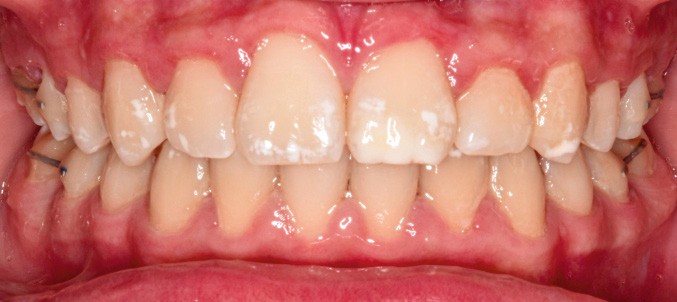

Une sur-correction de la rotation de 17 aurait été souhaitable pour optimiser l’alignement et les rapports occlusaux (fig. 2a-d).